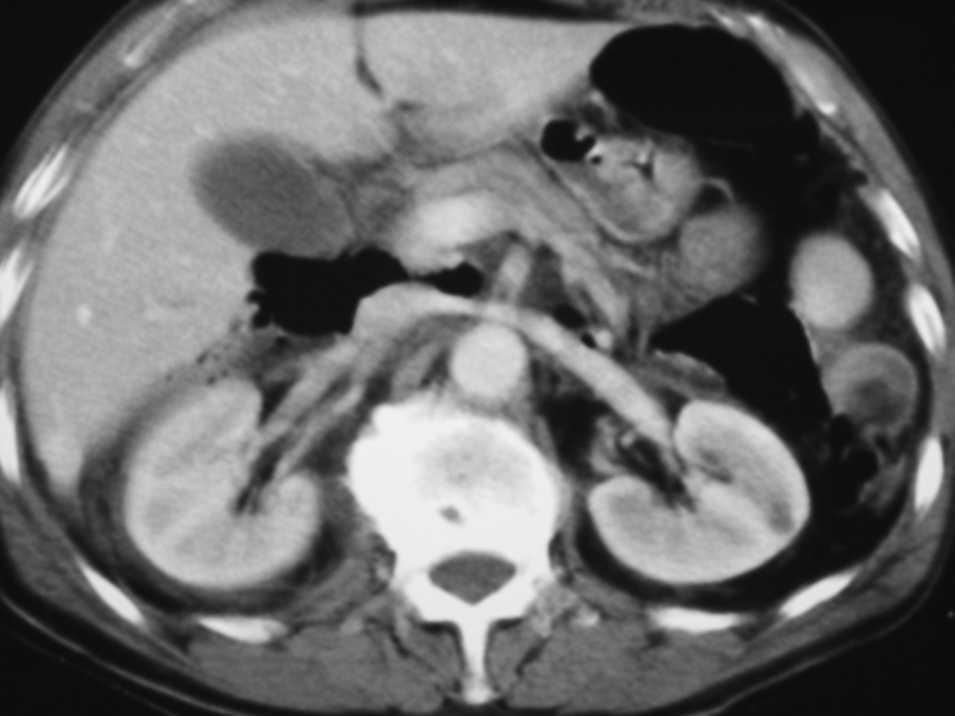

Varón de 73 años, que vive en un ambiente rural, sin alergias medicamentosas conocidas ni antecedentes clínicos de interés. Acude al servicio de urgencias con un dolor abdominal difuso, bastante intenso, tras haber tenido una caída accidental por las escaleras varias horas antes. A la exploración presentó un abdomen ligeramente peritonítico, doloroso, no distendido y sin hematomas visibles. La exploración neurológica, torácica y de las extremidades no reveló alteración alguna. En la analítica sólo destaca leucocitosis (13.500/μl) y el resto es normal. La radiografía abdominal mostró aire extraluminal en la zona superior derecha, y en la tomografía computarizada (TC) se confirma un neumoretroperitoneo (fig. 1), por lo que se procede a realizar una serie gastrointestinal con contraste hidrosoluble oral que demostró la existencia de varios divertículos a nivel de segunda y tercera porciones duodenales, con la extravasación de contraste en uno de ellos (fig. 2).

Fig. 1. Tomografía computarizada: se observa neumorretroperitoneo en la zona abdominal alta.